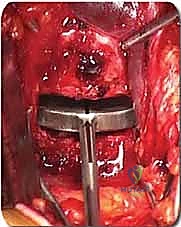

الخطوة 4: التحضير وزراعة القفص (Implant Insertion)

يتم قياس الفراغ المتبقي بدقة لاختيار الحجم المثالي للقفص الجراحي (Cage). يُصنع هذا القفص عادة من مادة PEEK أو التيتانيوم، ويتم حشوه بمادة عظمية (طعم عظمي ذاتي من المريض، أو طعم صناعي، أو بروتينات محفزة لنمو العظم BMP). يتم إدخال القفص بقوة في الفراغ، مما يؤدي فوراً إلى استعادة ارتفاع القرص الطبيعي وتوسيع المخارج العصبية (تخفيف الضغط غير المباشر).

الخطوة 5: التثبيت (Fixation)

لضمان أقصى درجات الثبات والسماح للعظم بالاندماج بمرور الوقت، يتم تثبيت القفص باستخدام شريحة معدنية صغيرة ومسامير من التيتانيوم تُثبت في الأجسام الفقرية من الأمام. في بعض الحالات، قد يرى الدكتور هطيف ضرورة إضافة تثبيت خلفي بمسامير عبر الجلد (Percutaneous Pedicle Screws) لزيادة الدعم.

الخطوة 3: إعادة بناء العمود الفقري (Reconstruction)

بعد إزالة الفقرة، يتبقى فراغ كبير جداً (Gap) في العمود الفقري. يجب سد هذا الفراغ لدعم وزن الجسم. يتم ذلك باستخدام:

* قفص قابل للتمدد (Expandable Cage): أسطوانة من التيتانيوم توضع في الفراغ ويتم توسيعها ميكانيكياً حتى تستقر بقوة بين الفقرة السليمة العلوية والسفلية.

* طعم عظمي هيكلي (Strut Graft): قطعة كبيرة من عظم بنك العظام يتم تشكيلها لتناسب الفراغ.

يتم حشو القفص بالطعوم العظمية لضمان الاندماج المستقبلي.

الخطوة 4: التثبيت القوي (Rigid Fixation)

نظراً لضخامة الفراغ الذي تم تعويضه، يتطلب الأمر تثبيتاً قوياً جداً. يتم استخدام شرائح تيتانيوم طويلة ومسامير من الأمام، وفي الغالبية العظمى من الحالات، يتطلب الأمر إجراء مرحلة ثانية لتثبيت العمود الفقري من الخلف بمسامير وقضبان لضمان استقرار البناء الجراحي بزاوية 360 درجة.